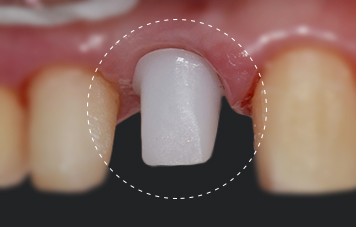

최종 결과의 자연스러움을 좌우하는 기둥(Abutment)

보이지 않는 차이가 결과를 만듭니다. 앞니 임플란트는 겉으로 보이는 치아뿐 아니라 보이지 않는 기둥까지 신경써야 합니다. 일반 금속 기둥이 아닌 세라믹 기둥을 사용하면 잇몸이 어두워보이지 않아 자연스럽게 보이며 잇몸 라인 유지에 유리합니다. 때문에 앞니, 웃을 때 많이 보이는 부위, 심미가 중요한 경우에 주로 사용됩니다.

세라믹 기둥(Abutment) 사용